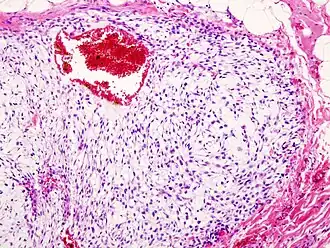

Le chondrosarcome est une tumeur maligne primitive osseuse avec des cellules tumorales présentant une matrice cartilagineuse hyaline[1]. Le chondrosarcome est la deuxième tumeur osseuse maligne en termes de fréquence, derrière l'ostéosarcome.

Il existe différents sous groupes histologiques de chondrosarcomes[5] : chondrosarcome central conventionnel, chondrosarcome secondaire, chondrosarcome mésenchymateux, chondrosarcome dédifférencié, chondrosarcome à cellules claires, chondrosarcomes périosté avec des risques métastatiques spécifiques.